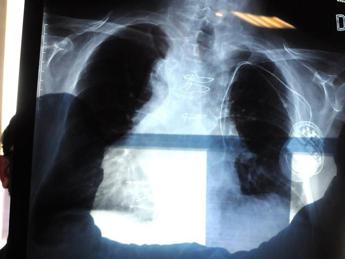

(Adnkronos) – "In Italia l'amianto è presente ancora ovunque e anche in modo insospettabile, senza che nessuno intervenga". Lo denuncia Antonio Giordano, oncologo italiano in forze negli Usa, dove è arrivata forte la testimonianza del giornalista Franco Di Mare che ha rivelato la malattia contratta presumibilmente negli anni trascorsi da inviato di guerra nei Balcani. La sua storia "ha scosso anche l'America. Siamo al suo fianco", dichiara all'Adnkronos Salute lo scienziato, presidente della Sbarro Health Research Organization (Shro) e professione alla Temple University di Philadelphia. Da un lato "urge eliminare definitivamente l'amianto presente nell'ambiente", dall'altro "serve mettere a punto un adeguato sistema di monitoraggio degli ex esposti", esorta Giordano, convinto che invece "interessi economici rallentano la ricerca scientifica". "Il mesotelioma pleurico – spiega l'oncologo – è un killer silente, ma allo stesso tempo è uno dei pochi tumori per cui l'eziologia è pressoché certa: lo sviluppo di questa neoplasia è certamente correlato all'esposizione a fibre di amianto". Giordano lo sa bene, sia perché "studio il mesotelioma da tantissimi anni" sia perché "posso definirmi un 'figlio d'arte'. Mio padre Giovan Giacomo Giordano – racconta – fu uno fra i primi scienziati, insieme al professor Cesare Maltoni del Collegium Ramazzini di Bologna, a studiare e a scoprire i gravissimi danni derivati dall'esposizione alle fibre di amianto e anche grazie alle sue ricerche l'amianto è stato messo fuori legge in Italia nel 1992". Un bando adottato "a livello europeo dal 1999".  Eppure di mesotelioma si continua a morire e accade "per due motivi", ragiona lo scienziato. Innanzitutto per la "lunga latenza clinica del tumore, considerando che tra l'esposizione al minerale e lo sviluppo della malattia possono intercorrere fino a 30 anni". E poi perché, "nonostante ogni attività di estrazione, commercio, importazione, esportazione e produzione di amianto, prodotti di amianto o prodotti contenenti amianto sia stata vietata, il materiale è ancora presente in grandi quantità – avverte Giordano – nei luoghi in cui non si è provveduto alla bonifica e allo smaltimento".  "L'aria avvelenata, anche dall'amianto, continua a far male" tanto che "ormai il rischio di sviluppare mesotelioma è diventato ambientale – precisa l'oncologo – piuttosto che professionale. Le peculiari caratteristiche fisico-chimiche dell'amianto giustificano il suo vastissimo utilizzo nell'edilizia per cui, se è presente in grandi quantità in zone come l'Italia, si può solo immaginare quante fibre di residui tossici ci possano essere in zone coinvolte da azioni belliche: residui derivanti dalla distruzione di edifici, dalla combustione e dall'ossidazione di inquinanti che restano in sospensione nell'aria, che penetrano nelle falde acquifere e nei terreni coltivati. Scenari che hanno visto coinvolto il giornalista Franco Di Mare".  Giordano ha all'attivo diversi lavori focalizzati sul mesotelioma pleurico, "poiché nonostante gli enormi progressi in ambito scientifico – puntualizza – questa neoplasia ancora oggi è orfana di marker diagnostici, prognostici e soprattutto di approcci terapeutici efficaci". Lo scienziato, campano 'doc' nato a Napoli, ha vissuto in prima linea anche la battaglia dei lavoratori dell'ex Isochimica di Avellino: "Una vera bomba ecologica", dice. "Il quartiere di Borgo Ferrovia, nel centro città – ricorda – ha respirato per anni un'aria intossicata dall'amianto. Lo certificano le perizie disposte dalla procura, a cui ho partecipato". "Ad oggi non vi è alcun test che da solo o in combinazione con altri possa essere utilizzato per campagne di prevenzione che possano essere avviate a livello di popolazione", fa notare l'oncologo. Bisognerebbe quindi affinare le armi diagnostiche per poter avviare un monitoraggio sugli ex esposti alle fibre d'amianto. "Invece oggi si assiste a un rallentamento degli studi", che per Giordano "potrebbe essere causato dai forti interessi economici alla base dell'industria dell'amianto". A maggior ragione, dunque, "nelle aree ad alto rischio di patologie asbesto-correlate – insiste lo scienziato – è indispensabile intervenire bonificando nel più breve tempo possibile. Non si può temporeggiare per motivi economici e condannare a morte migliaia di persone". —cronacawebinfo@adnkronos.com (Web Info)